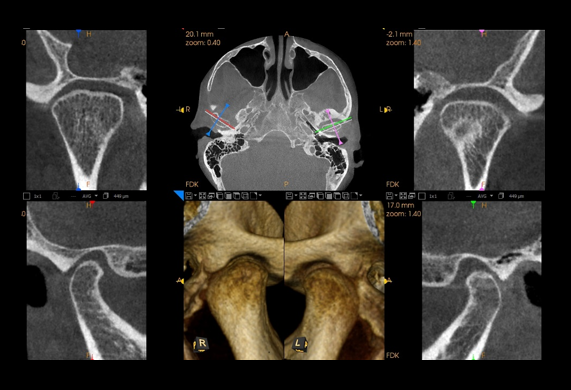

Stawy skroniowo-żuchwowe

Zatoki oboczne nosa (przynosowe)

Zatoki przynosowe